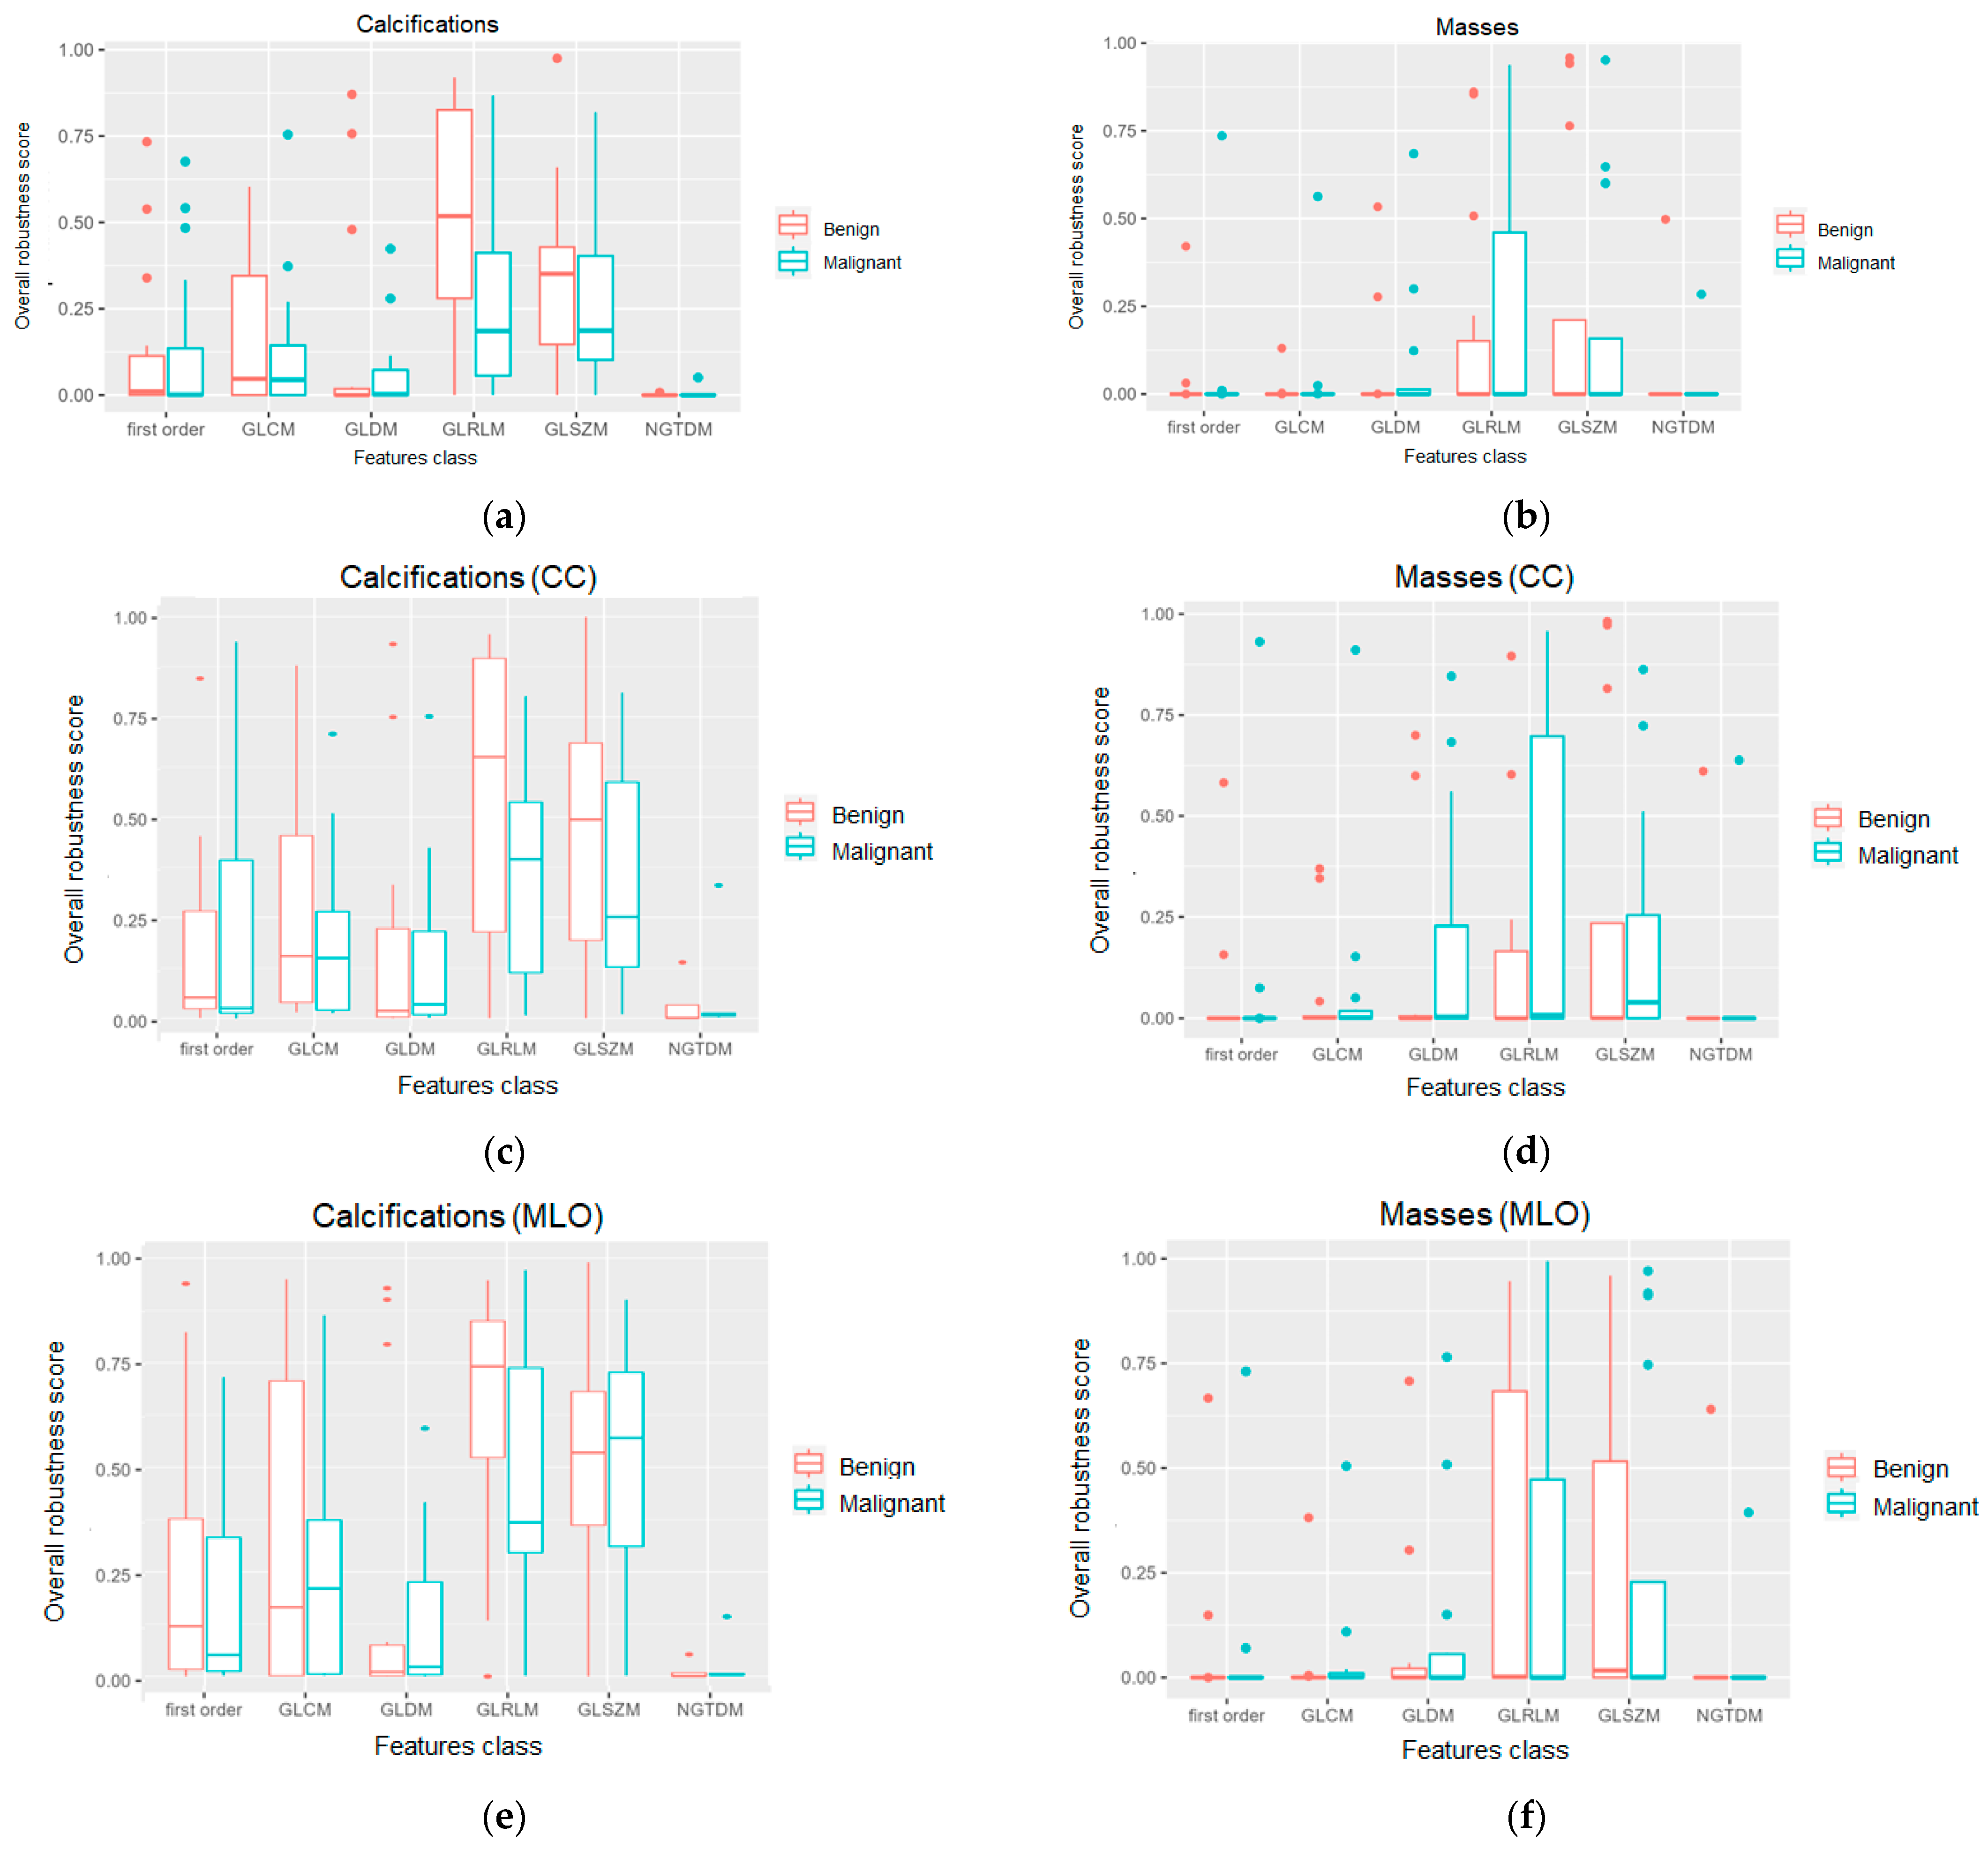

3. Results

4. Discussion